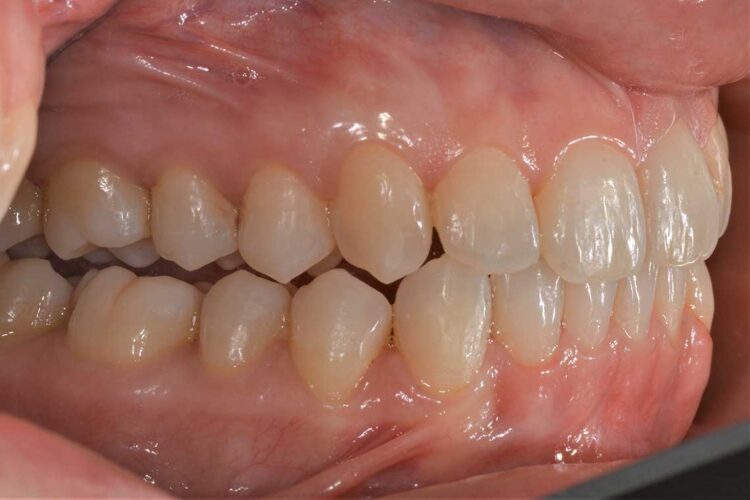

Ortodonzia allineatori – caso clinico 1